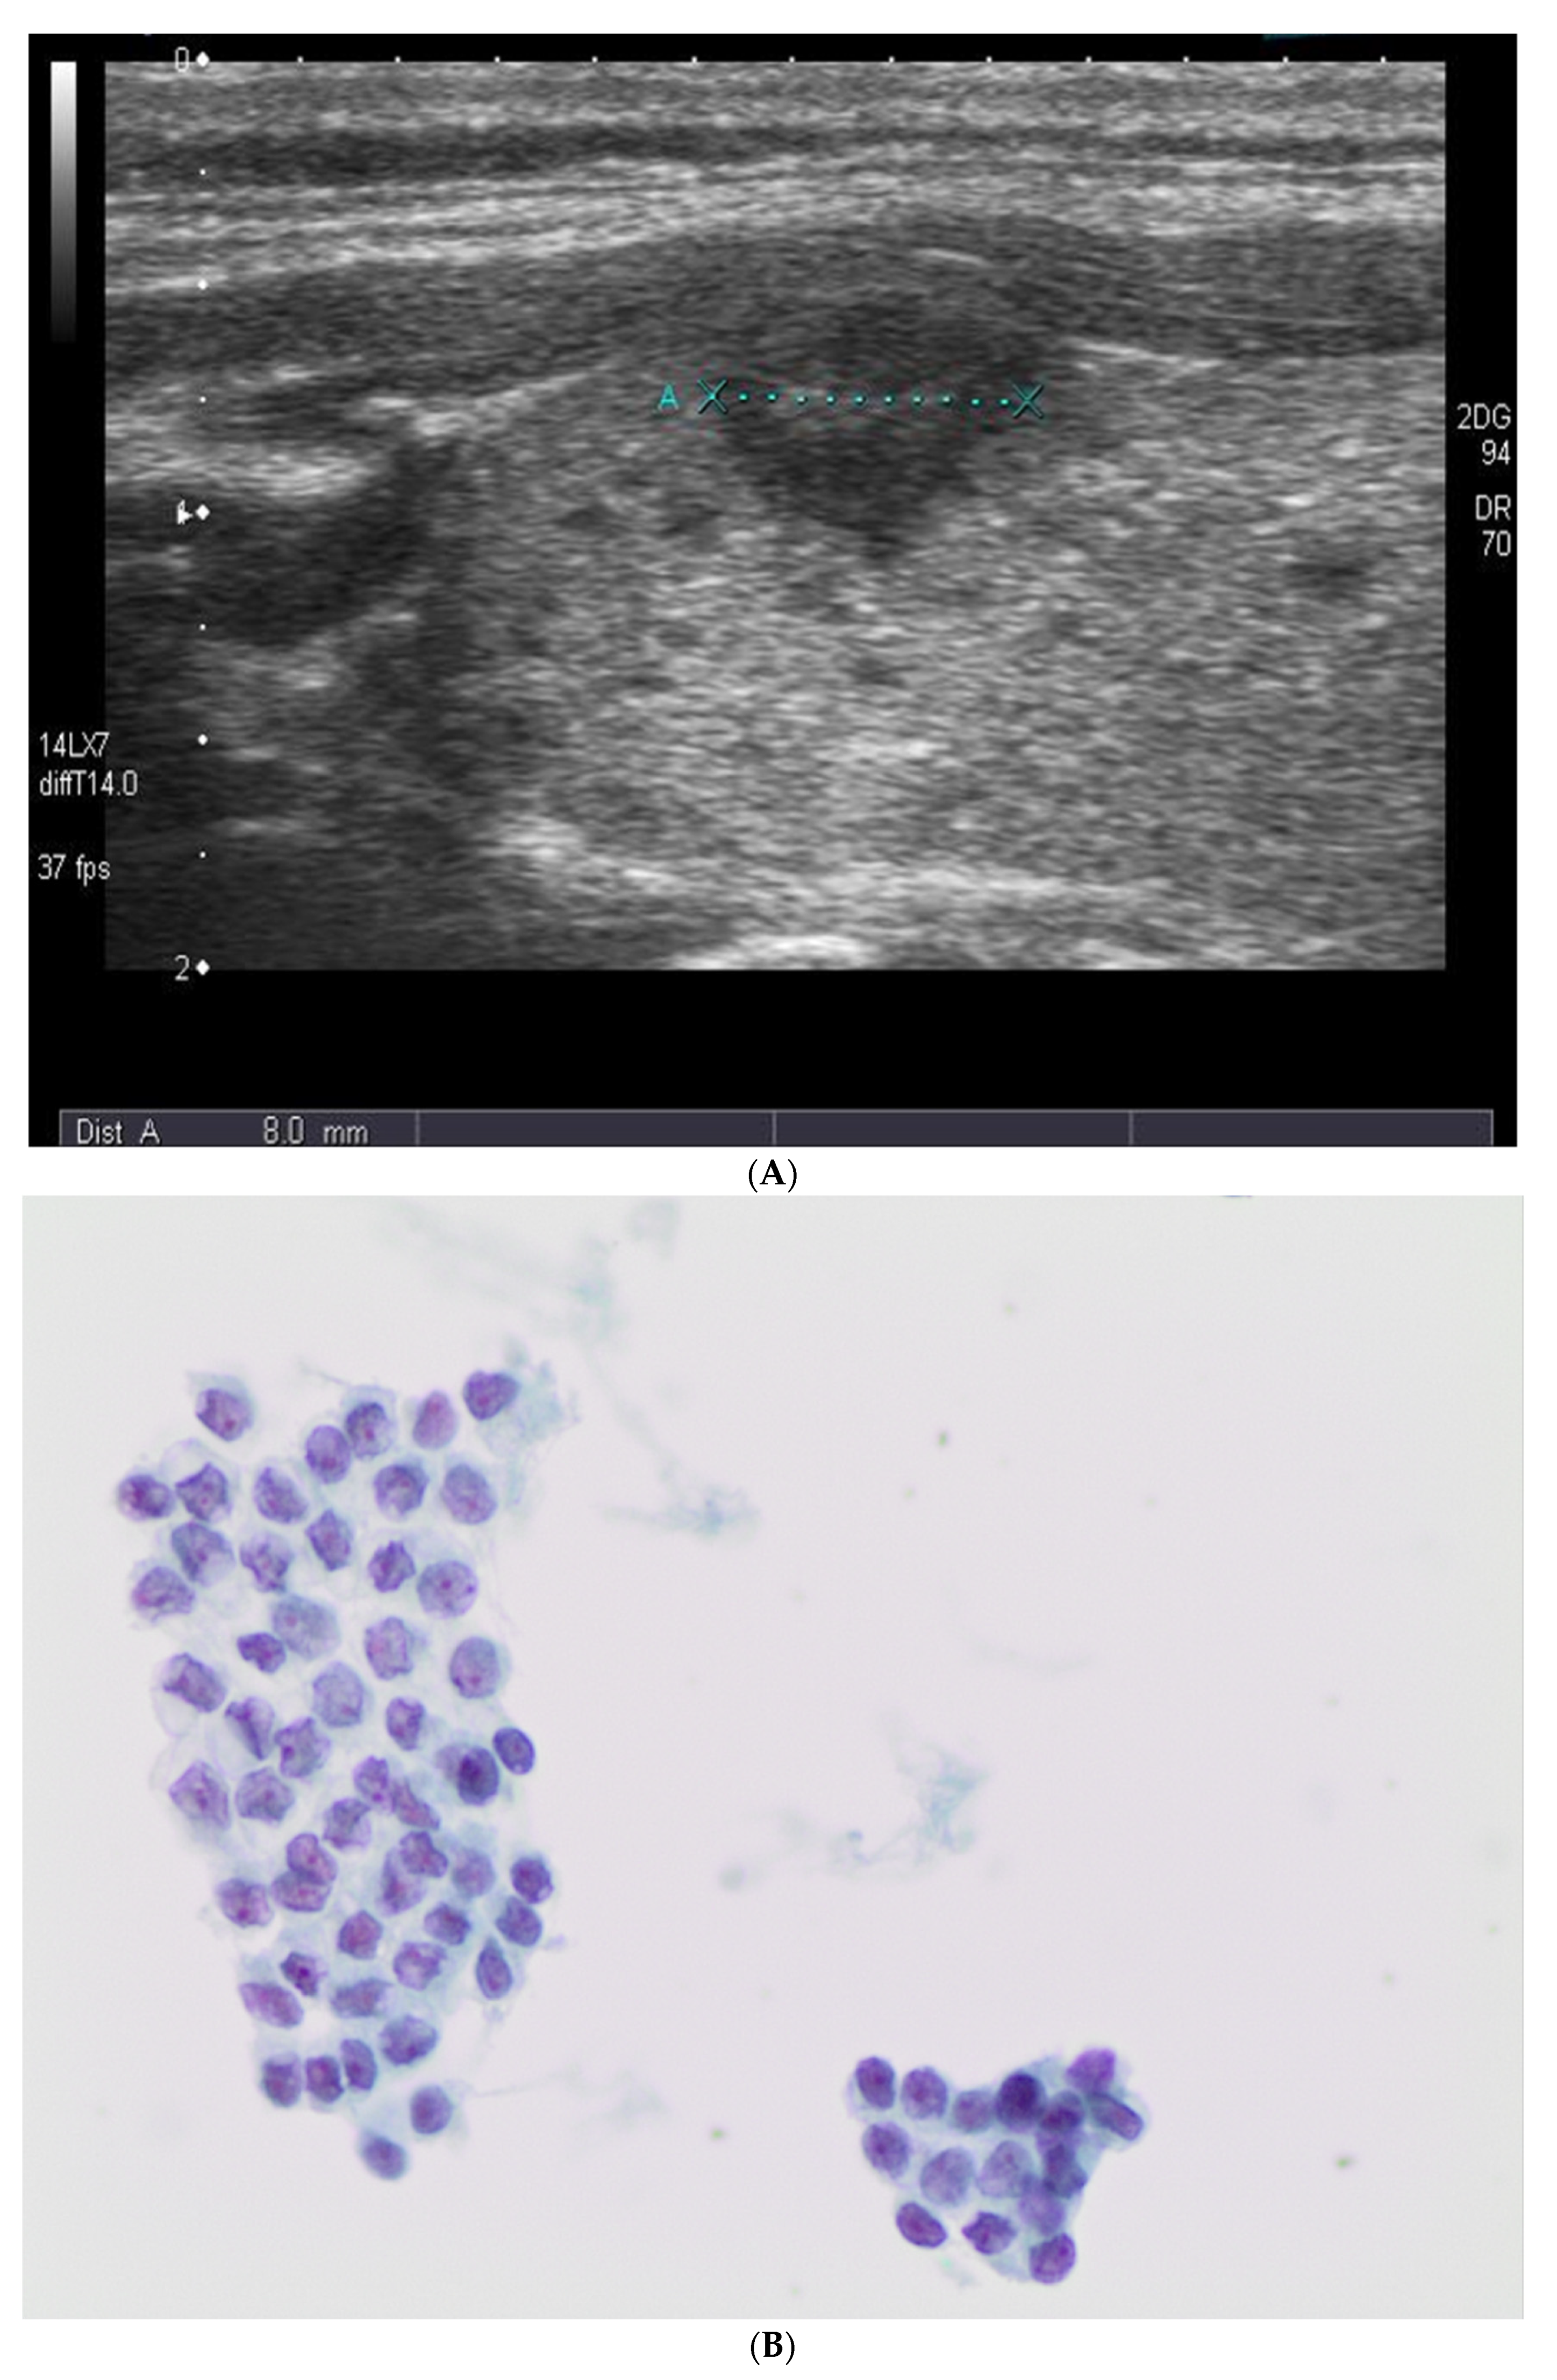

1. Introduction

2.2. Ultrasound Evaluation